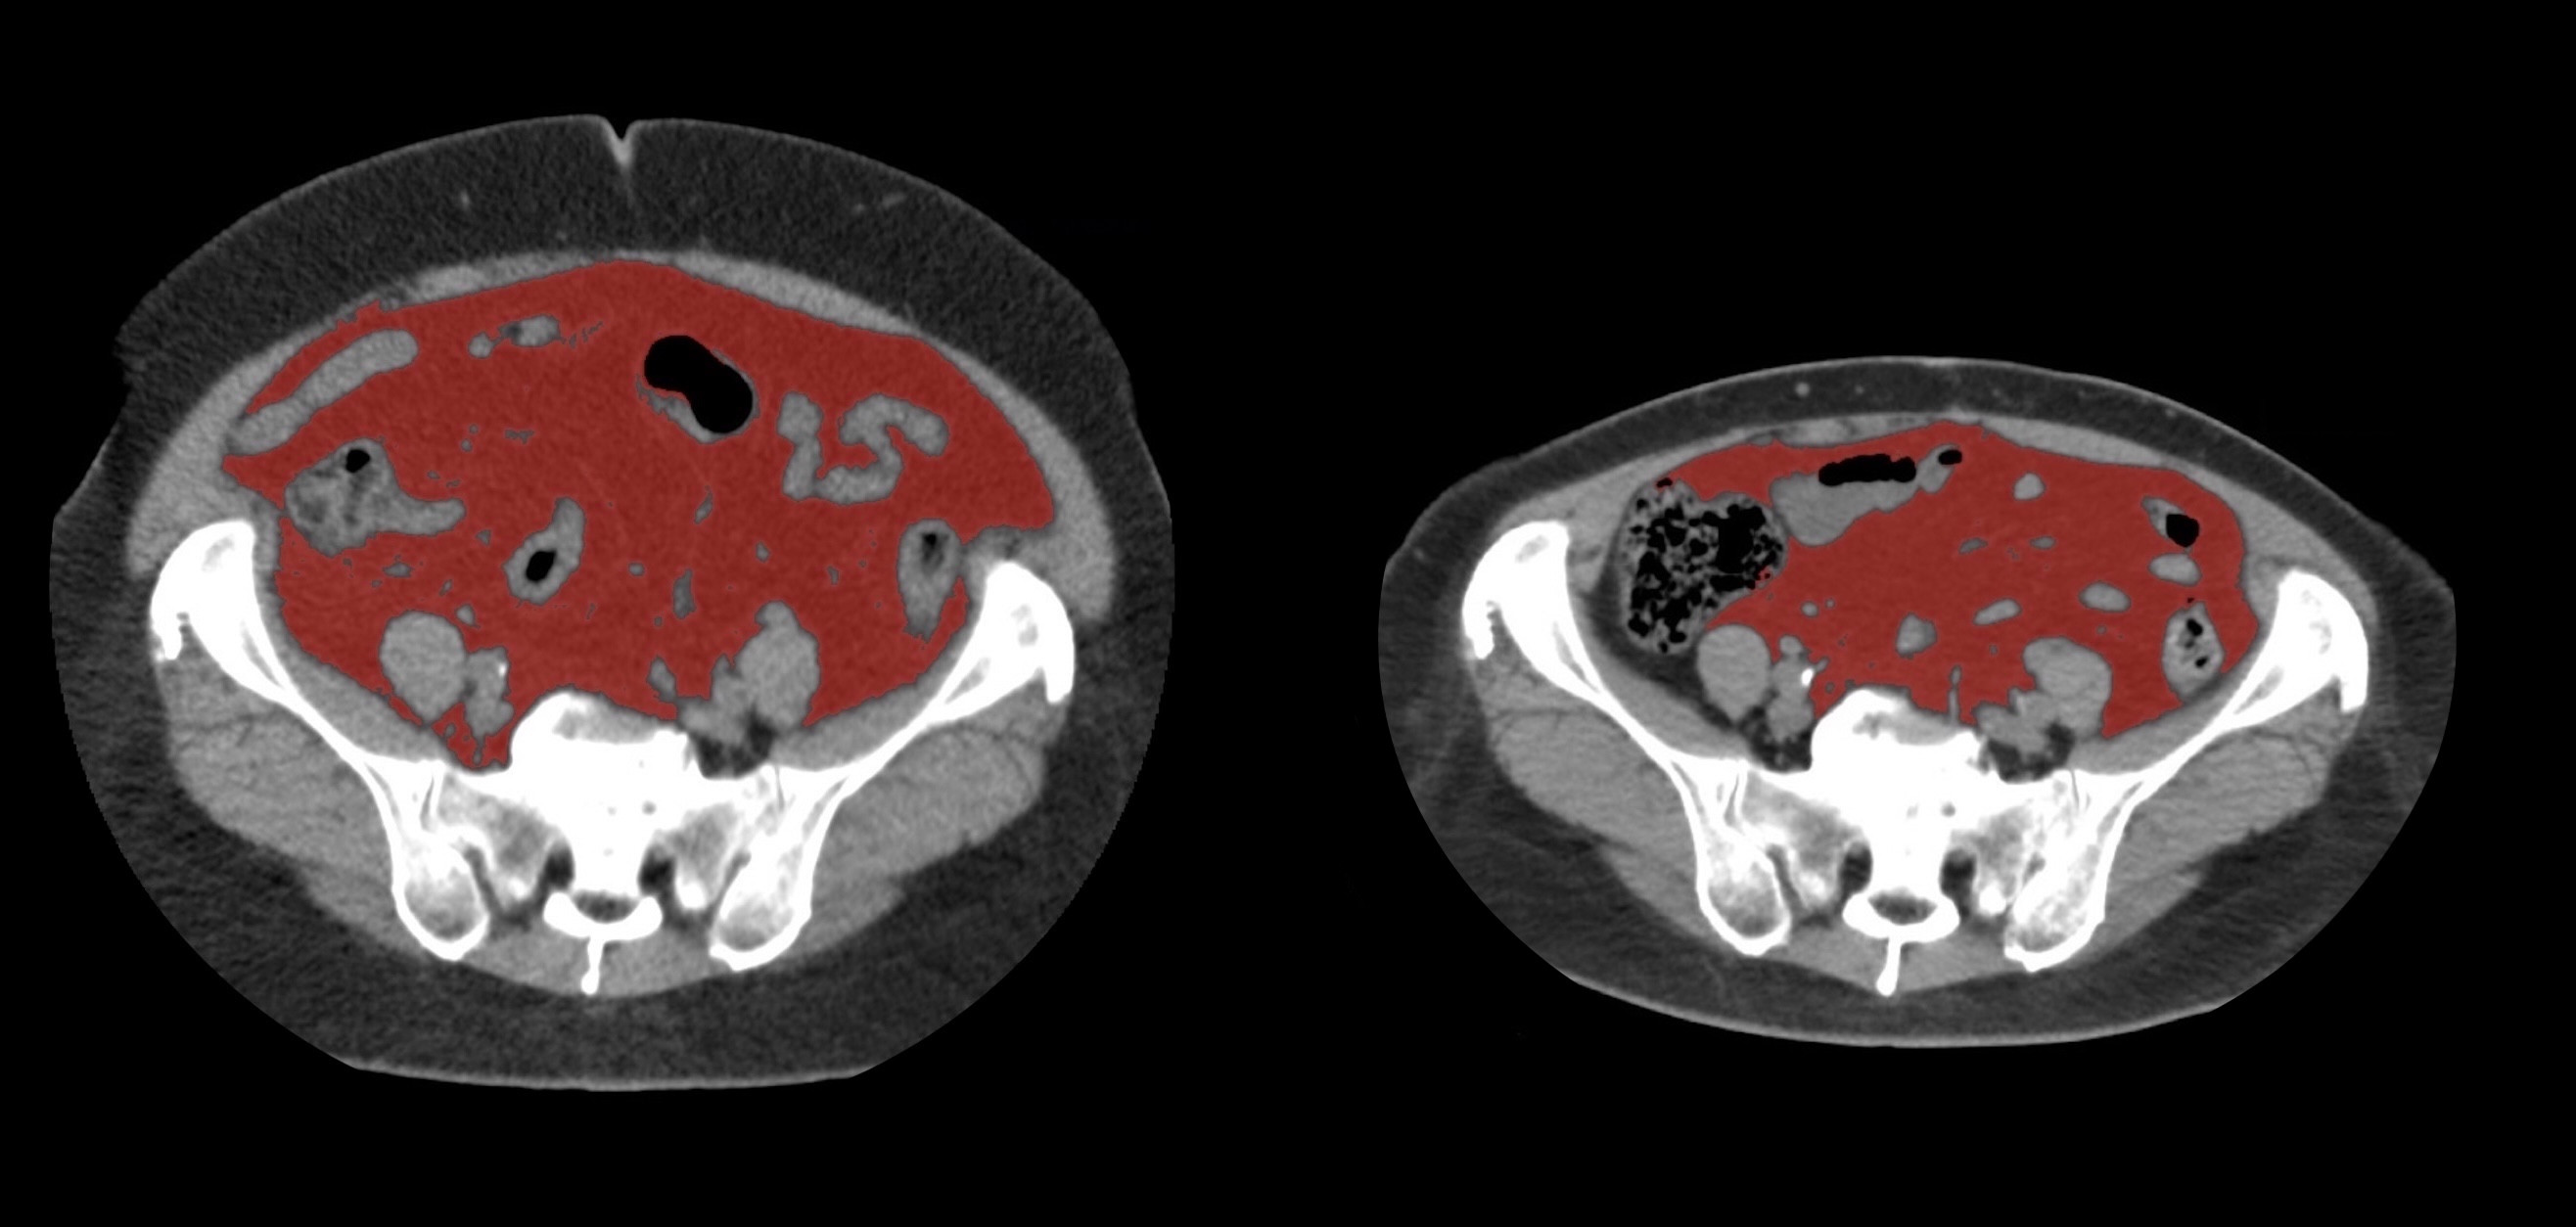

②

40代・女性(ご本人のご厚意で画像提供)

治療内容:チルゼパチド2.5mgの週1回自己注射による脂肪減少と脂肪肝改善

治療期間: 6ヶ月(26週)((用量は2.5mgから開始し最大で15mg。減量効果が得られる必要用量には個人差があります。))

費用:自由診療の場合は4400円(税込)×26(週)=114400円

想定されるリスク・副作用:下記に副作用を記載

※医療広告ガイドラインに準拠して表記

1:脂肪の減少

皮下脂肪の減少(赤色部分)

③

50代・男性(ご本人のご厚意で画像提供)

治療内容:チルゼパチド5.0mgの週1回自己注射による脂肪減少と脂肪肝改善

費用:自由診療の場合は7700円(税込)×26(週)=200200円